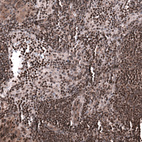

Immunohistochemical staining of human pancreas shows strong nuclear positivity in exocrine glandular cells and endocrine glandular cells.